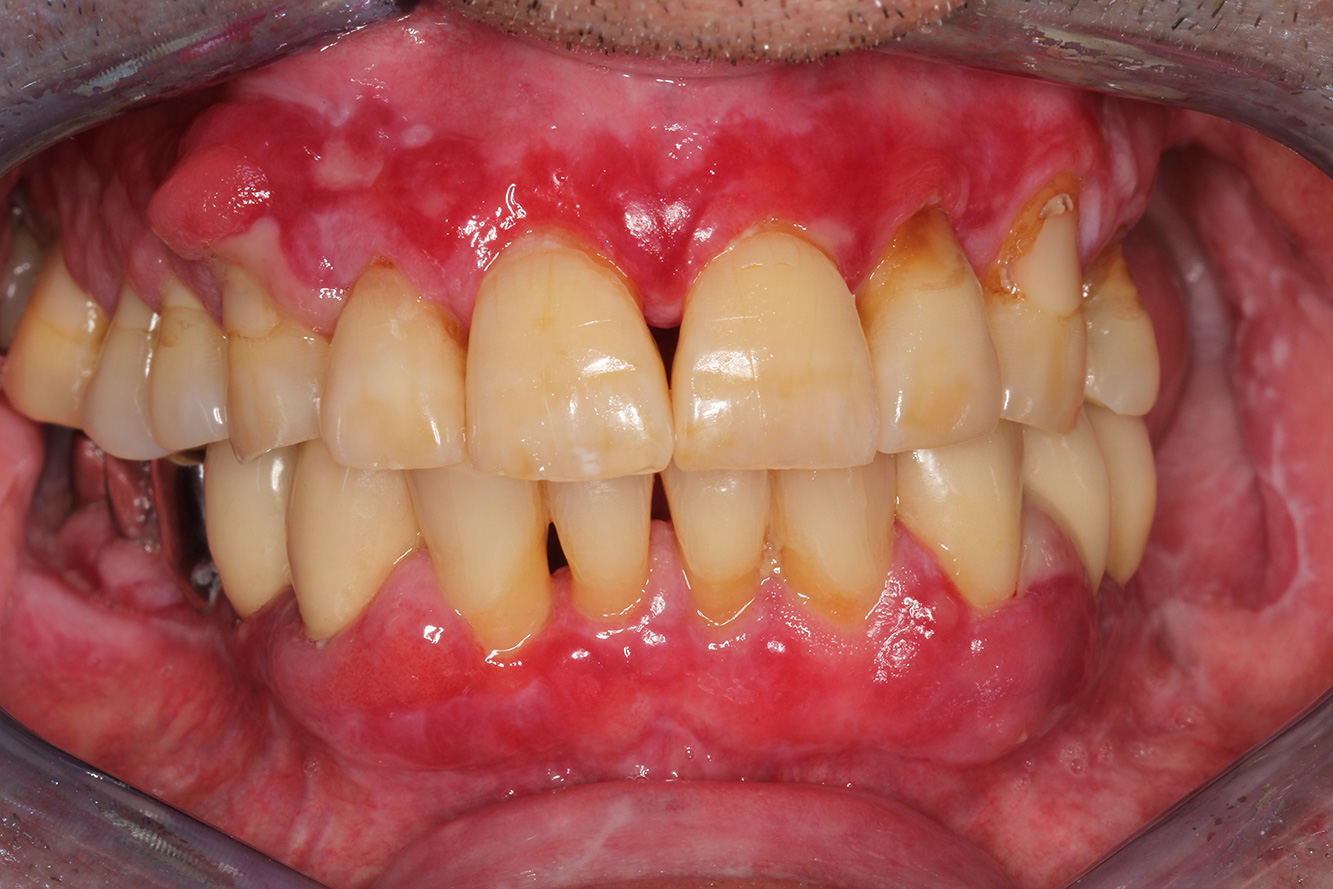

Si presenta un paziente di 71 anni che ha subito un trapianto di reni e con anamnesi di ipertonia (ipertensione). Considerata la sua storia clinica, serve una terapia a lungo termine con ciclosporina che ha un effetto immunosoppressivo e amlodipina che è specifica contro l'ipertensione. Il paziente riporta anche gengive sensibili e sanguinanti. Per quanto riguarda invece lo stato di salute orale, il paziente ha un restauro, presenta un'iperplasia gengivale marcata, una parodontite allo stadio II, grado B con tasche attive e un'iniziale carie radicolare al dente 22 e in più mancano otto denti. Dalla valutazione del rischio di carie si evince un rischio moderato di carie (API 60). Per la seduta di profilassi si possono formulare i seguenti consigli per il trattamento.

Sulla base dell'anamnesi del paziente si può rilevare un rischio particolare di complicazioni. Il paziente è immunodepresso (ciclosporina) in seguito al

trapianto di reni, quindi ha un sistema immunitario debole e necessita di una profilassi contro le infezioni (raccomandazione: 2 g di amoxicillina come antibiotico un'ora prima della seduta). Al tempo stesso, la terapia a lungo termine del paziente si traduce in un rischio aumentato di malattia, perché l'iperplasia gengivale riscontrata è associata proprio a questa terapia (20).

Bisogna quindi affrontare la situazione del paziente, in particolare per quel che riguarda training e istruzioni. Il paziente ha difficoltà a seguire una

corretta igiene orale a casa per via dell'iperplasia gengivale. Bisogna quindi parlare in modo chiaro con il paziente della sua maggior esposizione

alle infezioni così come della progressione e della ricomparsa dell'iperplasia (22). Al tempo stesso, bisogna istruire il paziente circa le tecniche di igiene

orale adatte per le sue esigenze specifiche.